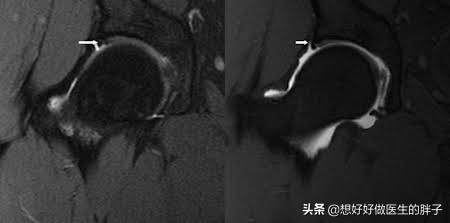

此外,完成x线检测并不一定意味着完全排除了病情,部分初期病变或髋部软组织异常在影像上难以显现,因此我们建议髋部疼痛者进行髋关节核磁扫描,对于单侧疼痛的情况,更应采用单侧髋关节核磁检查,这种检查能更准确地评估髋臼盂唇是否受损。